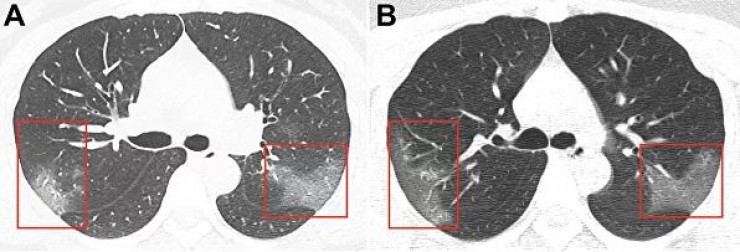

Изображения, опубликованные в журнале Radiology, получены в результате компьютерной томографии 33-летней женщины, госпитализированной в китайском городе Ланьчжоу с температурой 39 градусов.

На первом снимке видны помутнения, создающие "эффект матового стекла". На втором, сделанном три дня спустя, можно заметить, что пораженная область расширяется.

"На основании эпидемиологических характеристик, клинических проявлений, изображений грудной клетки и лабораторных данных был поставлен диагноз: "пневмония 2019-nСоV", - говорится в публикации.